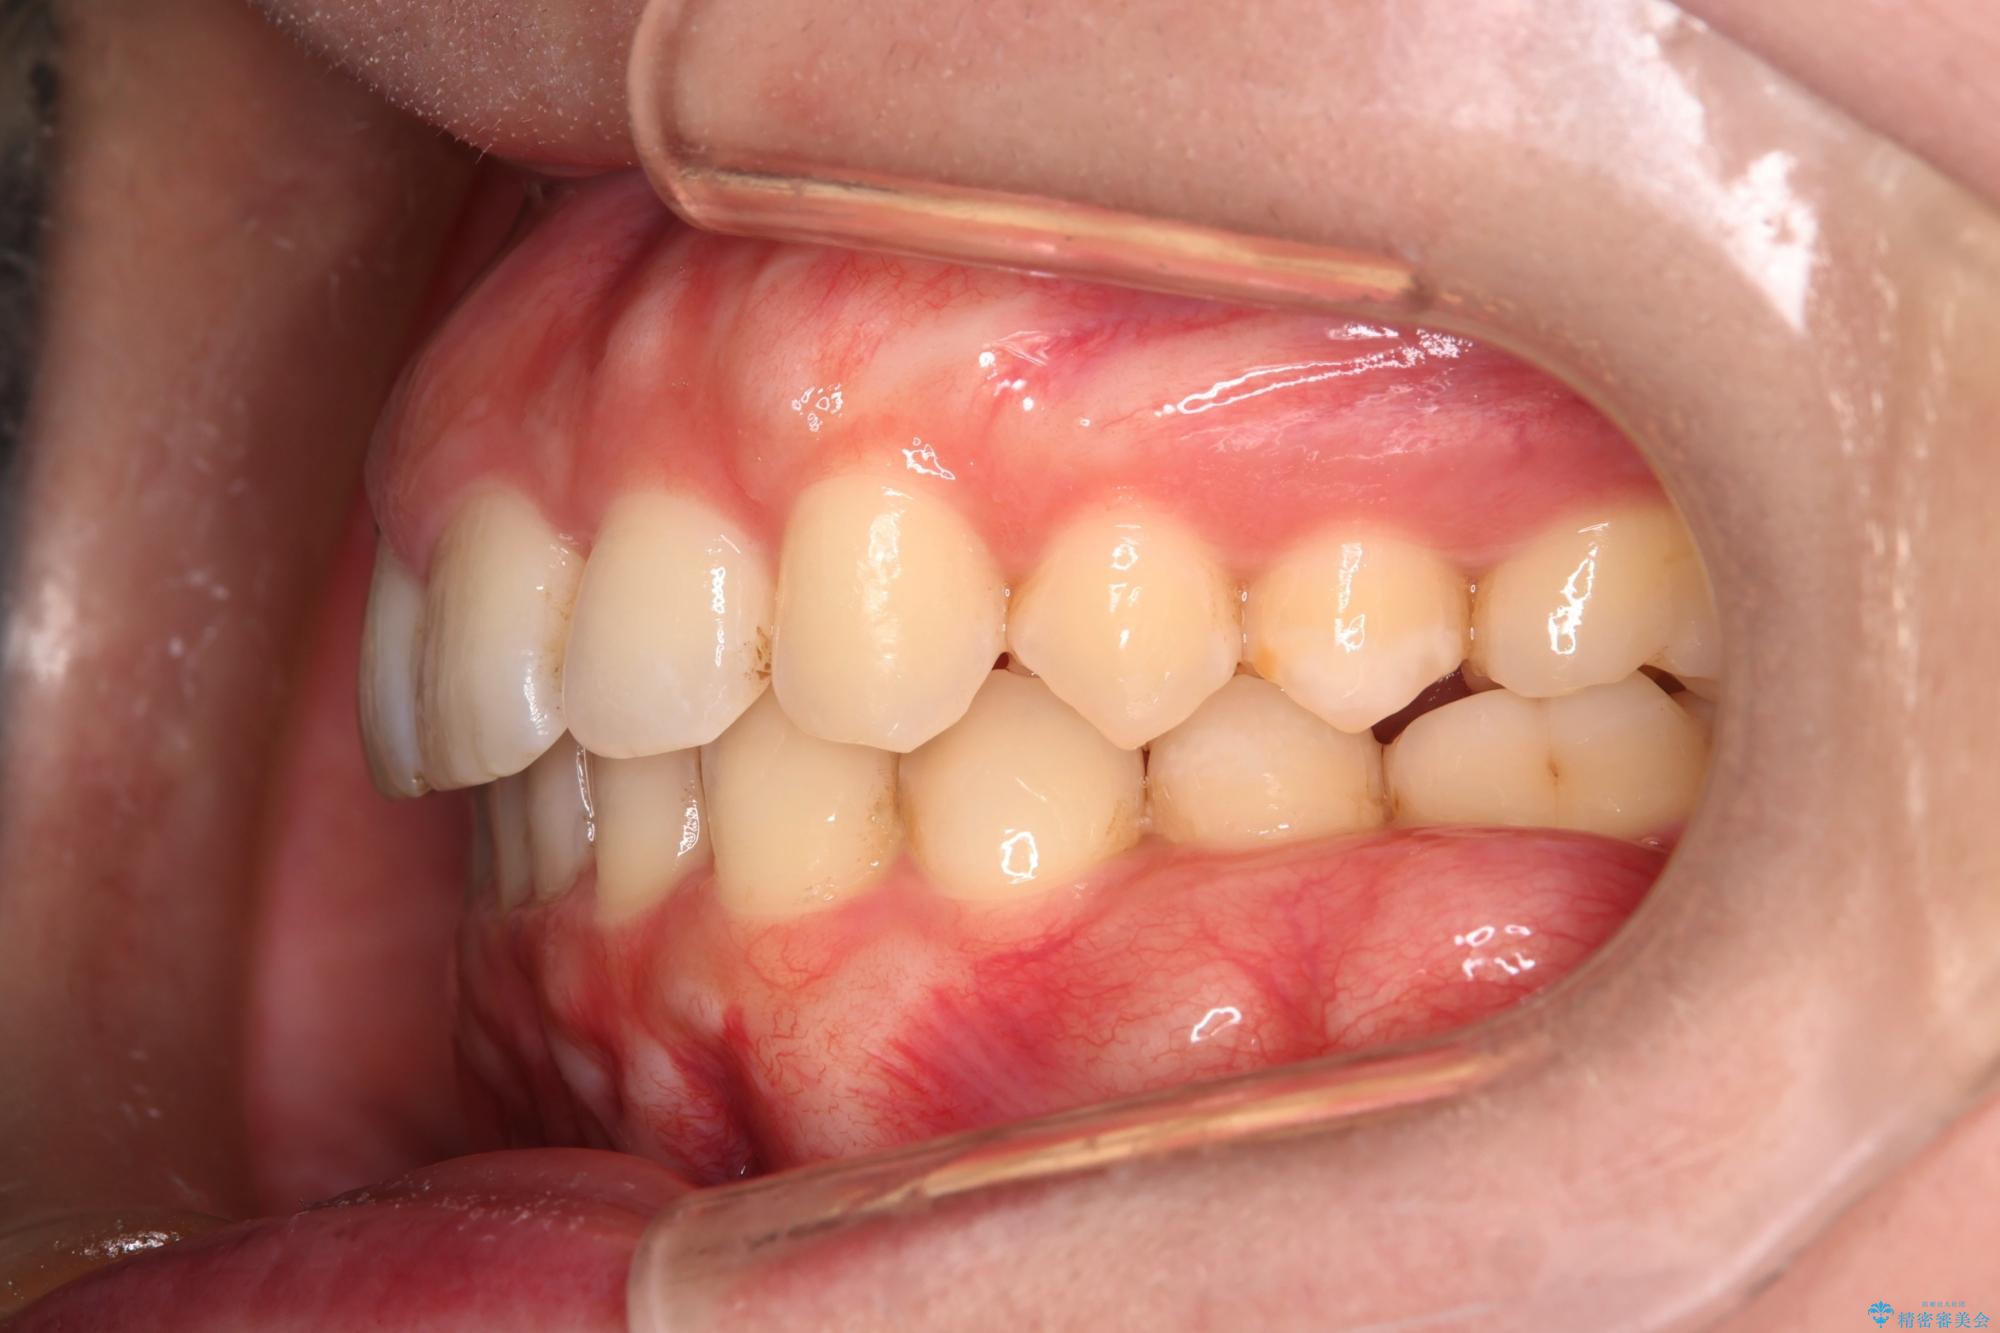

- 下の歯のがたつきを主訴に来院されました。

下の歯のがたつきと右の奥歯の噛みあわせ改善するために治療計画を立てることにしました。

右側臼歯部の咬合改善のために、臼歯部のみ部分的なワイヤー矯正を行い、咬合改善がみられてからインビザラインにて全体的な矯正を行なっていく治療計画を立てました。